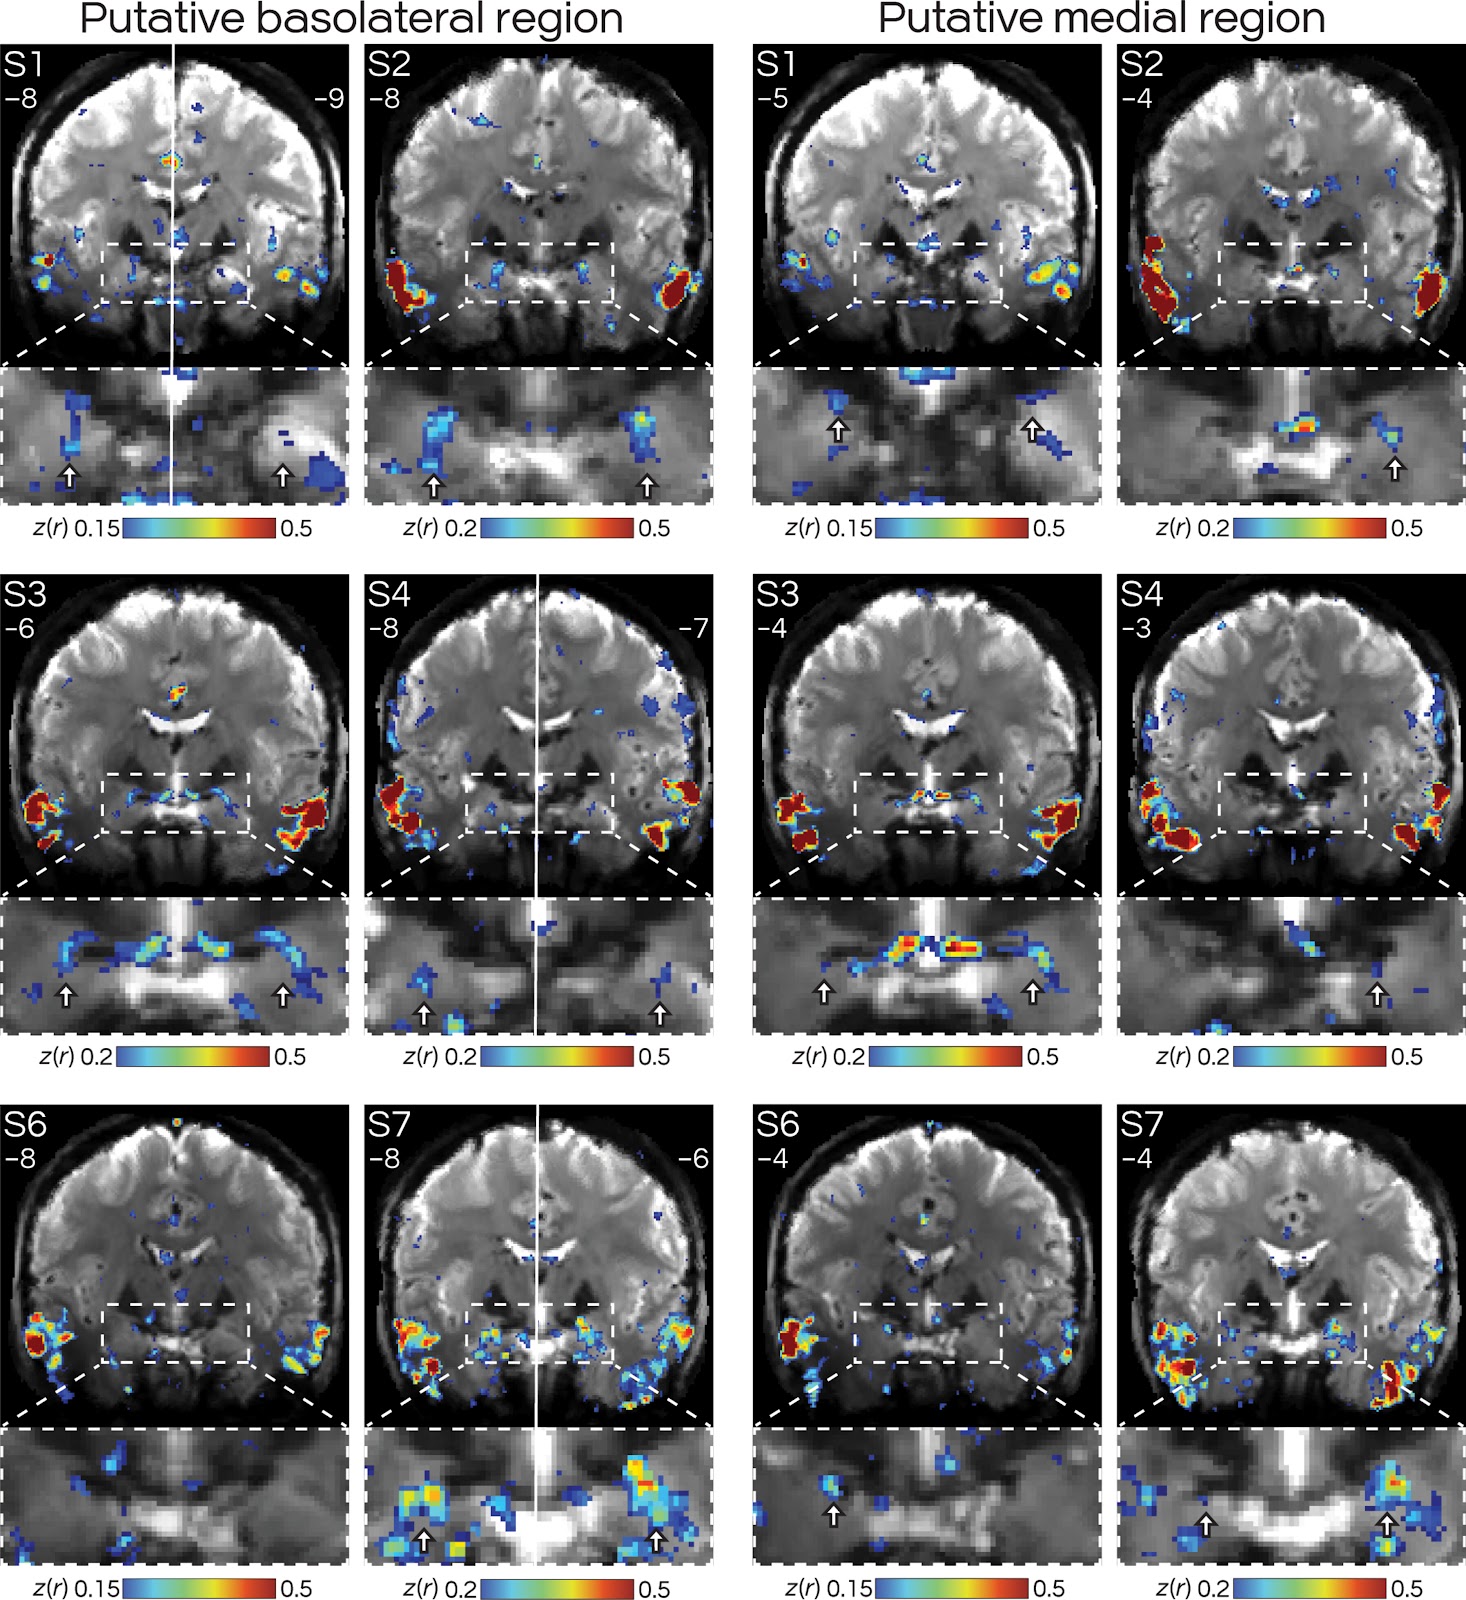

Fig. 6. Hand-drawn segmentation confirms that DN-B regions are in or near the MeA of the amygdala.

The MeA was hand drawn by an expert blinded to the network maps, following Noto et al. (128) and Mai et al. (130). All subjects displayed a region of DN-B that partially overlapped or was adjacent to the estimate of the MeA and that did not overlap with DN-A (see overlap map). Figure formatted according to Fig. 5.

Fig. 4. Basolateral and medial amygdala regions of DN-B are bilateral and replicate across participants.

Volume-based FC maps of DN-B are shown in coronal slices. Numbers refer to the MNI coordinate of each slice. (Left) Views around y = −6 to −9, where five of six subjects (exception: S6) displayed bilateral regions putatively in the basolateral amygdala. (Right) Slices around y = −3 to −5, where, in all six subjects, a distinct set of bilateral (three of six) or unilateral (three of six) regions could be seen putatively near the medial amygdala (Fig. 6). The white solid line in S1, S4, and S7 denotes that left and right hemispheres are from different slices. Arrows denote putative DN-B regions that were distinct from DN-A (see Figs. 5 and 6 for overlap map at these same slices and replications in figs. S6 and S7).